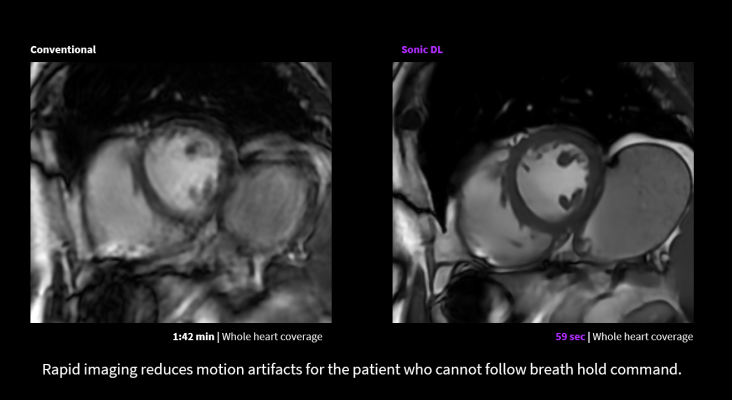

To address this need, GE HealthCare is introducing Sonic DL for cardiac MRI. Sonic DL technology is designed to scan up to 12 times faster compared to conventional methods, enabling rapid cardiac MR functional imaging in as fast as a single heartbeat, matching the speed of MRI to the speed of physiology. This advancement minimizes or removes the need for repetitive patient breath holds, simplifying procedures and expanding the pool of patients eligible for cardiac MRI to include arrhythmic patients and those with difficulty holding their breath.

Sonic DL’s capability to reduce cardiac MRI scan times by up to 83% also helps enhance productivity in radiology departments, streamlining workflows, alleviating backlogs, and reducing the burden on staff. Its cutting-edge technology tracks the beating heart with unparalleled image quality and overcomes the limitations of conventional acceleration techniques.